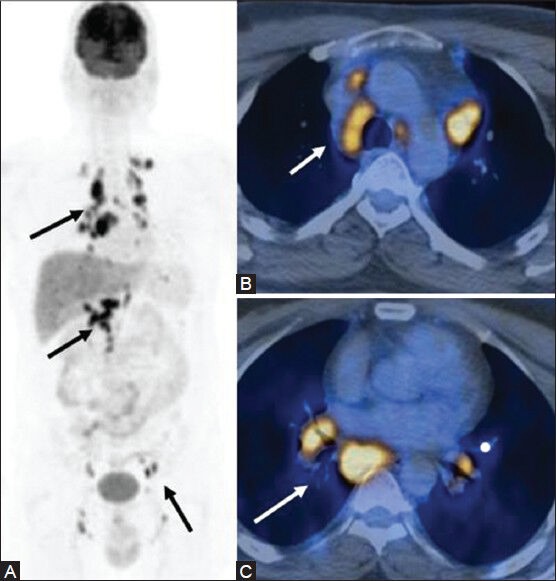

![The 4 stages of Lymphoma image by using PET/CT [17]. Focusing on ...](https://www.researchgate.net/publication/366208581/figure/fig4/AS:11431281106906315@1670896784740/The-4-stages-of-Lymphoma-image-by-using-PET-CT-17-Focusing-on-PET-MRI-scanners-since.png)